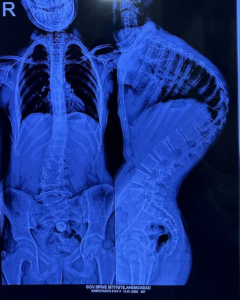

‘કાઇફોસ્કોલિયોસિસ’ એક ગંભીર બીમારી છે, જેમાં બાળકની કરોડરજ્જુ સાપની જેમ વાંકી વળી જાય છે, તેની સારવાર સામાન્ય મધ્યમ વર્ગ માટે એક સ્વપ્ન સમાન હોય છે. પરંતુ, ઈન્ડો-અમેરિકન સર્જરી કેમ્પના માધ્યમથી આ સ્વપ્ન હકીકત બન્યું છે.

સર્જરીની જટિલતા અંગે ઈન્ડો-અમેરિકન સર્જરી કેમ્પના ડૉક્ટરો જણાવે છે કે, આ એક અત્યંત જટિલ સર્જરી છે. સરેરાશ 4 થી 5 કલાક સુધી ચાલતી આ સર્જરીમાં કરોડરજ્જુને સીધી કરતી વખતે અત્યંત નાજુક ચેતાઓ (Nerves) અને રક્તવાહિનીઓ વચ્ચે કામ કરવાનું હોય છે. સર્જરી દરમિયાન મુખ્ય પડકાર સતત ‘ન્યુરો-મોનિટરિંગ’નો હોય છે. જો કોઈ પણ પગલું ખોટું પડે, તો મુખ્ય રક્તવાહિનીની ઈજાને કારણે દર્દીનો જીવ જઈ શકે છે અથવા જીવનભરનો લકવો (Paralysis) આવી શકે છે. આ જોખમને ખાળવા માટે અમેરિકન ન્યુરો-મોનિટરિંગ ટીમ અને એનેસ્થેસિયા નિષ્ણાતોએ પણ ટેકનિકલ સહયોગ આપ્યો હતો.

આર્થિક પાસા પર નજર કરીએ તો, આ પ્રકારની જટિલ સર્જરીનો ખર્ચ ખાનગી હોસ્પિટલોમાં રૂ. ૫ થી ૧૦ લાખ જેટલો આંકવામાં આવે છે. ગવર્નમેન્ટ સ્પાઈન ઈન્સ્ટિટ્યૂટ વર્ષ દરમિયાન આવી ૩૦ થી ૪૦ સર્જરીઓ કરે છે. આ કેમ્પમાં ૯ વર્ષના એક બાળક પર ‘ગ્રોઇંગ રોડ સર્જરી’ કરવામાં આવી હતી, જે આધુનિક મેડિકલ સાયન્સનું શ્રેષ્ઠ ઉદાહરણ છે. આ ‘ગ્રોઇંગ રોડ સર્જરી’ બાળકની ઉંમર વધવાની સાથે તેની કરોડરજ્જુને સીધી રાખવામાં મદદ કરશે.